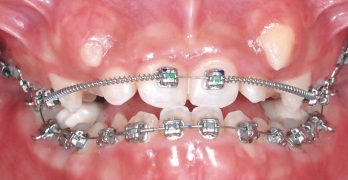

BDR CCCV: Tratamiento sin extracciones, pseudoclase 3, apiñamiento severo y mordida profunda y cruzada anterior

Terminamos la semana, con una nota de nuestro infame Baúl del recuerdo. La nota se llama Tratamiento sin extracciones, … [Leer más...] acerca de BDR CCCV: Tratamiento sin extracciones, pseudoclase 3, apiñamiento severo y mordida profunda y cruzada anterior